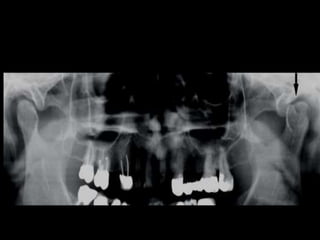

Ankylosis treated with total joint prosthesis

Panoramic view shows prosthesis (arrow), consisting of artificial fossa (fixed with six

titanium screws in temporal bone), and artificial condylar process (fixed with seven titanium

screws to mandibular ramus